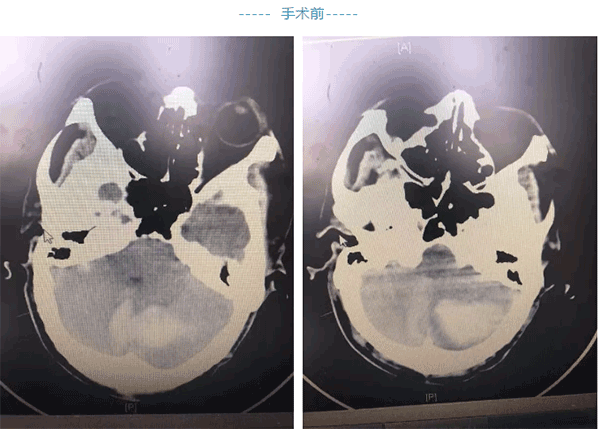

近日,我院神经外科收入一例小脑出血病人,男性,80岁,术前病人病情呈进行性加重直至昏迷(期间家属犹豫,拒绝手术),病人血小板极低(报危急值)27x10⁹/L,经我院神经外科杨为卓主任反复向患者家属交代病情,最后家属同意手术。

杨主任为患者输注血小板纠正血小板低下,行后颅窝开颅手术治疗,术后患者神志转清,但患者在呕吐时误吸窒息,出现呼吸衰竭、左心功能衰竭,两个脏器功能衰竭死亡率50%以上,加之患者系老年高龄,死亡率、抢救难度大大增加。转送ICU经护理的积极配合历经层层关隘,患者最终肺功能和心脏功能逐渐恢复正常。